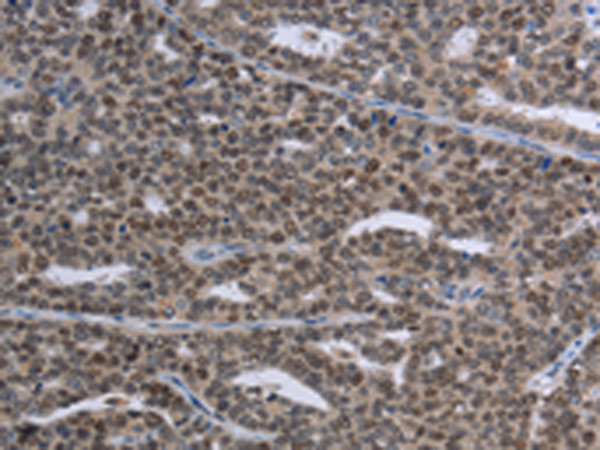

分类: 科研抗体货号: P05037别名:应用: WB,IHC反应种属: Human